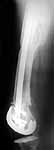

A male 41 years old transferred to our unit with 3 week old femoral fracture near the knee prosthesis after a mimimal fall. In 1994 he sustained multiple injury with open patella fracture (complicated with septic arthritis), and ipsilateral femoral shaft fracture treated by ex-fix.

TKA performed in 1998. In 2001 he got a periprosthetic fracture which was treated nonoperatively and healed with ~1 cm dorsal displacement of the distal femoral block. Knee ROM prior the recent injury was about 90-95 degrees. He didn't use walking aid.

Images attached.